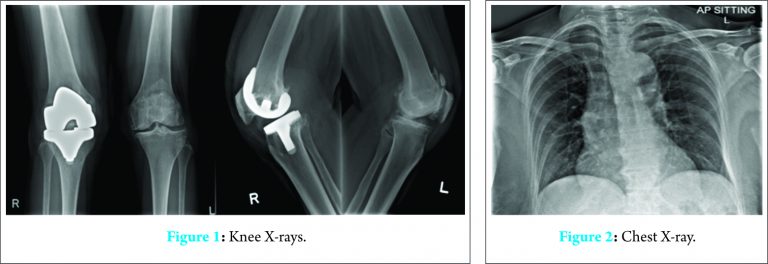

Inflammatory markers were markedly raised with C-reactive protein (CRP) 333 mg/L, white cell count 16.26 × 109/L and erythrocyte sedimentation rate 84 mm/h. Other blood tests were within normal range. Her right knee X-ray showed no features of prosthesis loosening or periprosthetic fractures (Fig. 1). Chest X-ray showed no evidence of consolidation in the lungs (Fig. 2).